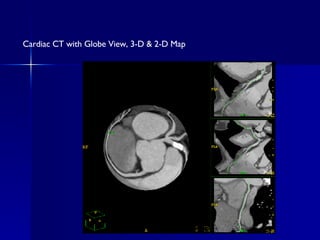

Cardiac CT with Globe View, 3-D & 2-D Map